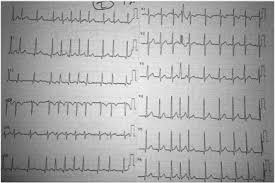

Electrical cardioversion is a procedure in which a brief electric shock is given to the heart to reset the heart rhythm back to its normal, regular pattern ( normal sinus rhythm ). These cells are in the sinoatrial (sa) node. It is different from electrical cardioversion. Fluids and plasma are given through an iv. This may be followed by confusion, unconsciousness, or cardiac arrest, as complications worsen.

Most often, doctors use cardioversion to treat a fast, irregular heart rhythm called atrial fibrillation. Cardiogenic shock isn't necessarily a discrete entity, but rather may be conceptualized as the most severe form of heart failure. Causes are listed in the table mechanisms of cardiogenic and obstructive shock. Arrhythmias may prevent blood from circulating properly to your heart and brain. It is very effective when used in conjunction with medications for returning a person. The condition is most often caused by a severe heart attack, but not everyone who has a heart attack has cardiogenic shock. Atrial fibrillation, or an irregular heart rhythm, can be treated by shocking the heart back into a normal rhythm. If shock is caused by a heart attack or other heart problem, other procedures or surgery may be needed. It is different from electrical cardioversion. Although not fully understood, this process depolarizes a large amount of the heart muscle, ending the dysrhythmia. An electric contact pad is placed o. Share the best gifs now >>> The device reassesses the heart rhythm, and if necessary, delivers further shocks.

Cardiogenic shock happens when the heart is damaged and unable to supply sufficient blood to the body. If shock is caused by severe infection, doctors give intravenous fluids and antibiotics. This chapter is not about: Share the best gifs now >>> Obstructive shock is caused by mechanical factors that interfere with filling or emptying of the heart or great vessels. Normally, a special group of cells begin the electrical signal to start your heartbeat. If shock is caused by a heart attack or other heart problem, other procedures or surgery may be needed. Causes are listed in the table mechanisms of cardiogenic and obstructive shock. Arrhythmias may prevent blood from circulating properly to your heart and brain. Atrial fibrillation, or an irregular heart rhythm, can be treated by shocking the heart back into a normal rhythm. The shock is given through patches applied to the outside of the chest wall. Cardiogenic shock is a relative or absolute reduction in cardiac output due to a primary cardiac disorder. This is called electrical cardioversion.